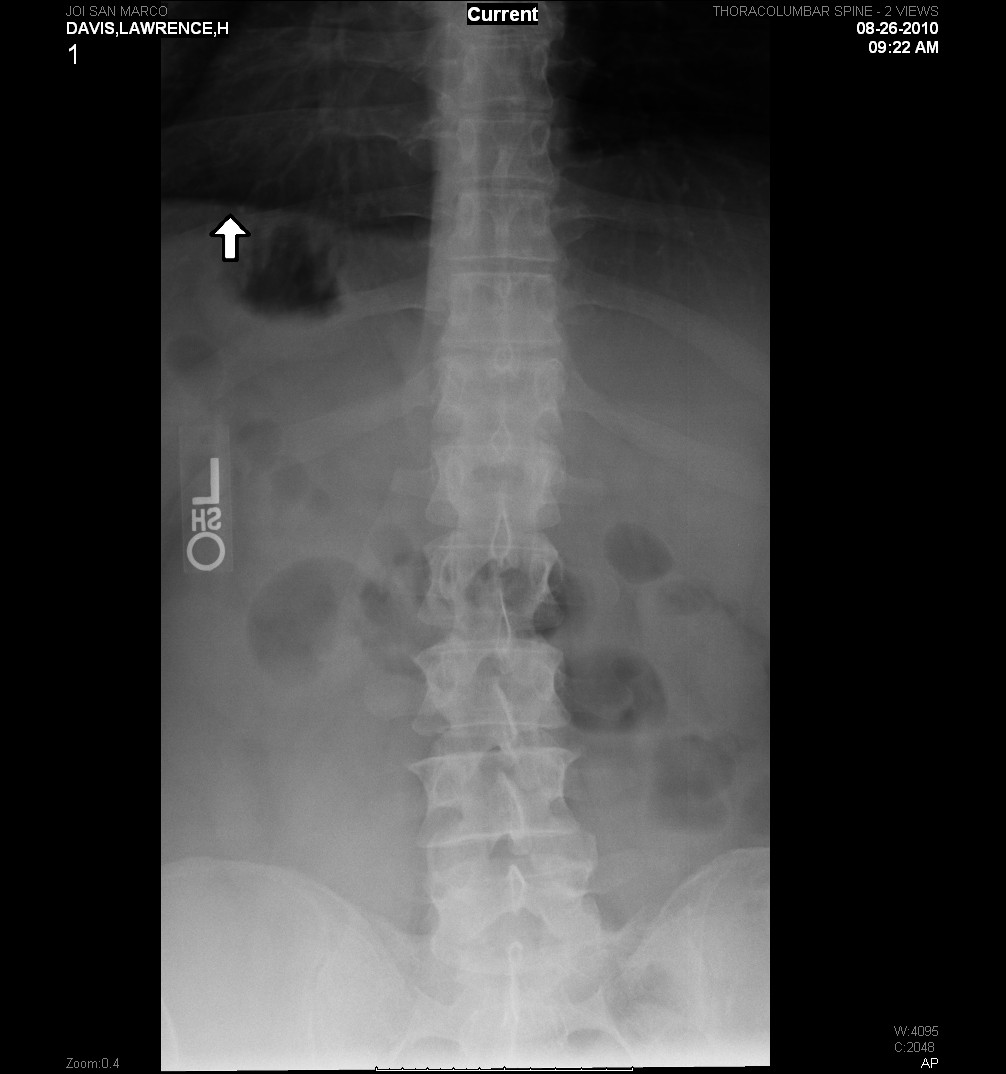

Here are a couple of shots from todays x-ray.

The pictures do not reflect the fracture as well as the film from the hospital. I’ll try to get that film and place it here.